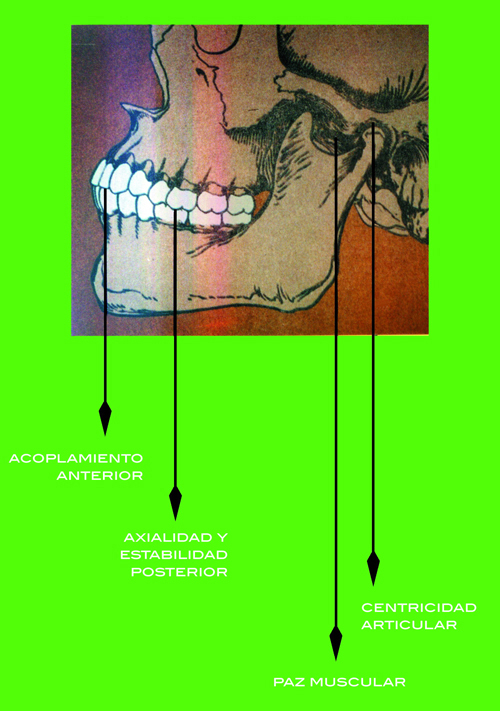

Deberíamos tener en cuenta que un paciente al que vamos a ponerle implantes, como cualquier otro tratamiento, debería ser un paciente al cual el bruxismo ya se le ha resuelto.

Ningún paciente debe ser Rehabilitado antes de conseguir lo que yo llamo PAZ DEL SISTEMA:o sea:

ACOPLAMIENTO ANTERIOR

AXIALIDAD Y ESTABILIDAD POSTERIOR

PAZ MUSCULAR

Y

CENTRICIDAD ARTICULAR.

Si tu paciente recibió implantes y esta dentro de este estado de Paz…de TODO el sistema…

pués no es necesario generalmente hacer mas que unos pequeños ajustes oclusales según el esquema que presento en este trabajo que has leido.